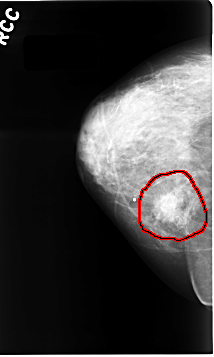

FILE: C_0064_1.RIGHT_CC.OVERLAY

TOTAL_ABNORMALITIES 1

ABNORMALITY 1

LESION_TYPE CALCIFICATION TYPE AMORPHOUS DISTRIBUTION CLUSTERED

LESION_TYPE MASS SHAPE IRREGULAR MARGINS SPICULATED

ASSESSMENT 5

SUBTLETY 5

PATHOLOGY MALIGNANT

TOTAL_OUTLINES 1

BOUNDARY